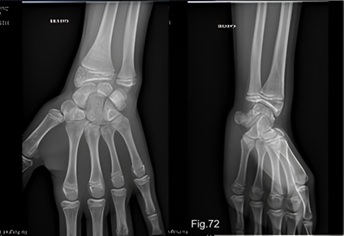

Cas clinique 13 : Entorse du poignet (massage)

Un garçon de 14 ans s'est blessé au poignet gauche il y a deux semaines en soulevant un téléviseur lourd. La douleur se situe au niveau de l'apophyse styloïde de l'ulna, à l'endroit où il a subi une intervention chirurgicale un an auparavant. Il avait alors une fracture du radius distal avec une fracture du styloïde de l'ulna, qui a été réduite orthopédique et ostéosynthésée par broches de Kirschner. Après ablation des broches, tout s'était bien passé et il n'avait plus de problèmes (Fig.72). Cependant, il s'est à nouveau blessé à cet endroit il y a deux semaines.